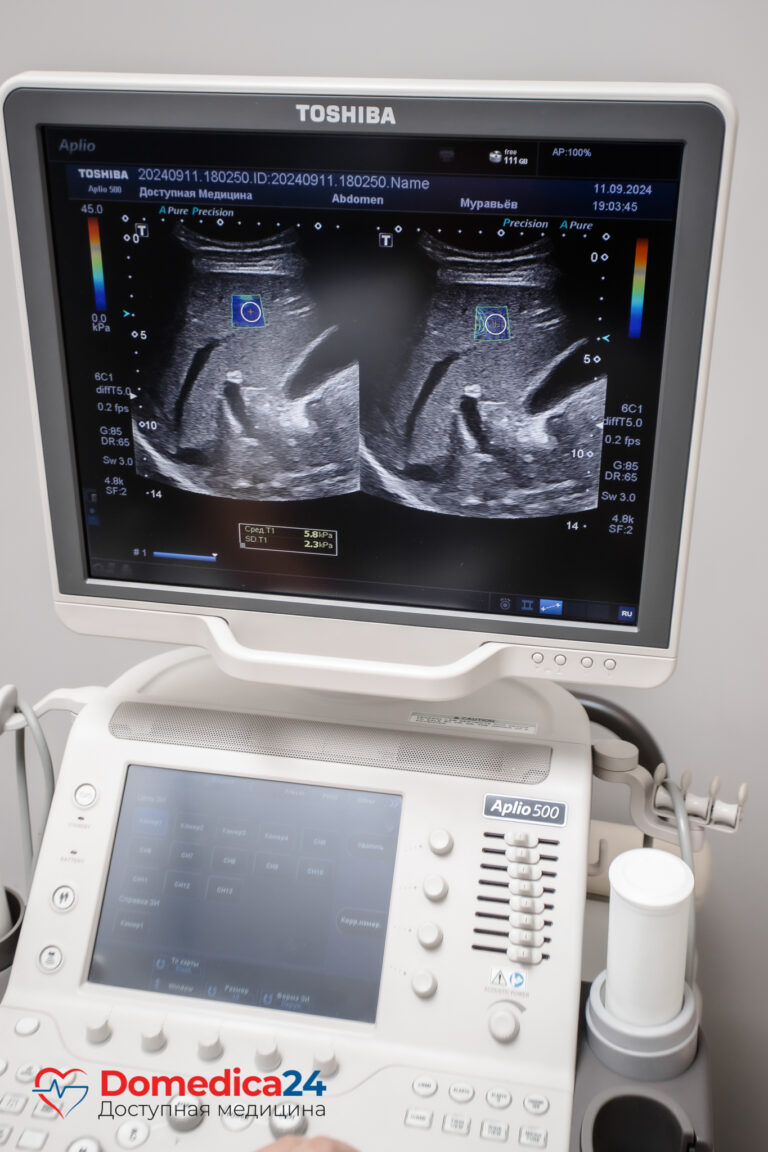

Здоровые ткани наделены определенной, достаточно высокой эластичностью. В то время как патологические, заболевшие ― более жесткие. Поверхностно расположенные образования врач может прощупать пальцами, определить нарушения в глубоко расположенных органах помогает такая аппаратная методика как эластография. Это один из вариантов ультразвукового исследования: аппарат испускает ультразвуковую волну, она достигает тканей разной плотности и визуализируется на экране в виде цветных пятен и количественных показателей ― килопаскалей, соответственно шкале Метавир.

С помощью эластографии, или как еще называют этот метод ― фибросканирования, возможно определить степень поражения печени при ее диффузном разрастании. Из-за вирусных гепатитов В и С, аутоиммунных поражений или алкоголизма гепатоциты гибнут и замещаются фиброзной тканью, а это постепенно ухудшает работу печени. Эластография позволяет отследить начавшееся диффузное заболевание еще на ранней стадии и начать лечение, когда оно еще эффективно.

Степень фиброза по шкале Метавир.

Фибросканирование печени не требует особой подготовки, однако проводится натощак. Обнажив правый бок, пациент укладывается на кушетку на спину с заведенной за голову правой рукой. Врач прикладывает УЗИ-датчик к коже и водит им в области печени, наблюдая за ее состоянием на экране. Затем пишет заключение. Все вместе занимает около 25 минут.